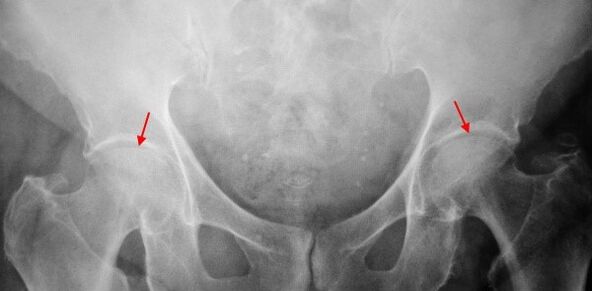

Op der X-Leiden vum Patient vun der COXHHHTRESE vum 1. Grad, mëller Ännerungen sinn bestëmmt: moderéiert ongläiche Verengung vum Joint Spalt, souwéi Knöchkugel vum Acetabulumen ronderëm den ACTETBULS VUN DER MECHT A RIGHERS

A x -ray Biller fir Coxarkosis vum 2. Grad, bedeitende ongläiche Verengung vum gemeinsame Spalt (méi wéi d'Halschent vun der normaler Héicht) gëtt bestëmmt) bestëmmt. De femorale Kapp gëtt e bësse wéi no uewen an der Gréisst erhalen an d'Metalls wäert onbedéngt ginn. Bonue Wuesstumen mat dësem Grad vu Coxhartrosis erschéngen net nëmmen op der Regioun, awer och um baussenzege Rand vum Acetabulum a gitt de Knorpel.

Bannen fir Béiragographs fir Coxarkroder vum 3. Grad, eng schaarf Verléissung vun der Gepompe, eng ausgeglach Expäter vum Oberschenknothéiken.